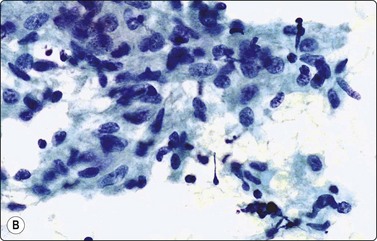

image image

Fig. 5.5 Reactive lymphadenopathy, follicular

Smear derived from reactive follicle. Centroblasts, centrocytes, small lymphocytes and tingible body macrophages with nuclear fragments (A, MGG; B, Pap; HP).